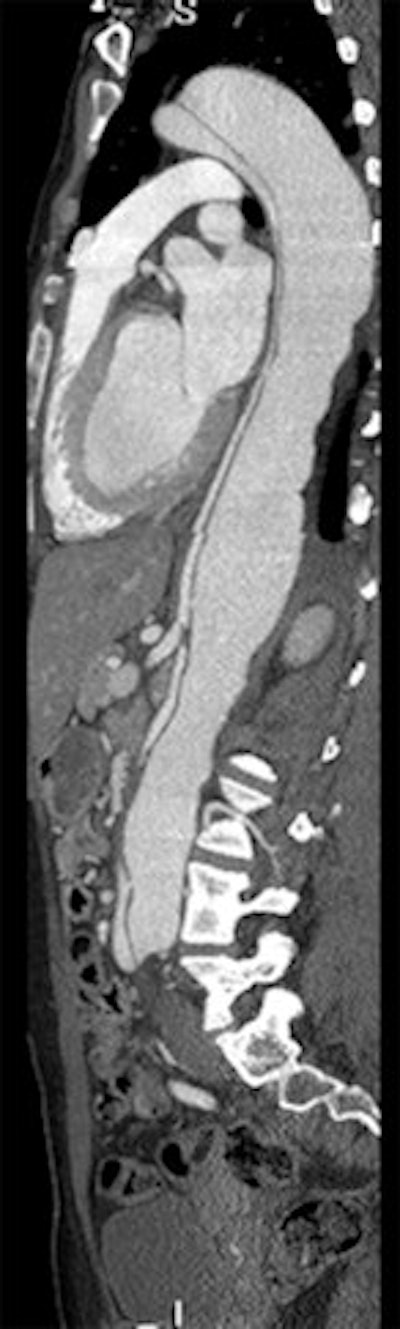

Images of the whole aorta were acquired using a wide-volume protocol; each volume was scanned in a single heartbeat with 16-cm anatomic coverage. The second volume was positioned to cover the whole heart to ensure that all the segments of coronary arteries were in the same dataset. The table is stationary during each acquisition, and then moves to the next location for the next CT data acquisition. Patient is a 23-year-old woman with Marfan syndrome combined with coronary-pulmonary fistula, and a Stanford type A aortic dissection. All images courtesy of Dr. Yu Li.

For all the power of modern CT scanners to generate exquisitely detailed images of the vasculature, scanning the aorta without gating is risky because artifacts in the ascending aorta can simulate the appearance of a dissection flap, leading to an incorrect diagnosis of dissection. In their study, Li and colleagues aimed to investigate the feasibility of using a prospective ECG-gated wide-volume protocol in CTA of the whole aorta and coronary arteries (CA).

CTA of the aorta is a common imaging technique due to its speed and resolution, according to the researchers. But motion in the ascending aorta can be a problem without ECG gating. Using 320-detector-row CT, image quality is acceptable throughout, and for Stanford type A aortic dissection, CTA showed the relationship between the intimal flap, and the aortic valve and the coronary ostium "without obvious motion artifacts," they stated.